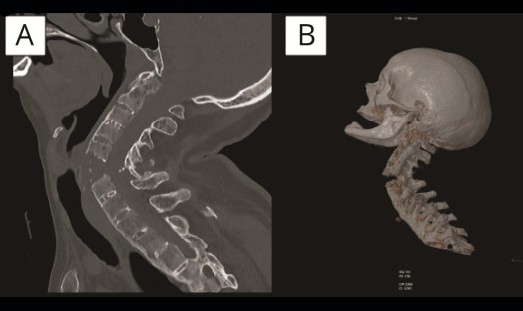

Las radiografías del caso se viralizaron en redes sociales.

A pesar de que el informe médico de este caso clínico corresponde a septiembre de 2021, en redes sociales se compartieron las imágenes de diagnóstico a finales del pasado mes de octubre, generando mucha expectación entre el sector sanitario de nuestro país. Muchos facultativos emitieron su opinión en Twitter sobre estos tratamientos al descubrir en el informe del hospital que la paciente tenía anquilosis de la columna cervical, y seguramente una "espondilitis anquilosante", un diagnóstico incompatible con ciertas acciones sobre el cuello. "Todos los fisioterapeutas y quiroprácticos deben saber que NO se manipula el cuello en estos pacientes debido al alto riesgo de fractura", apuntaba un reumatólogo.